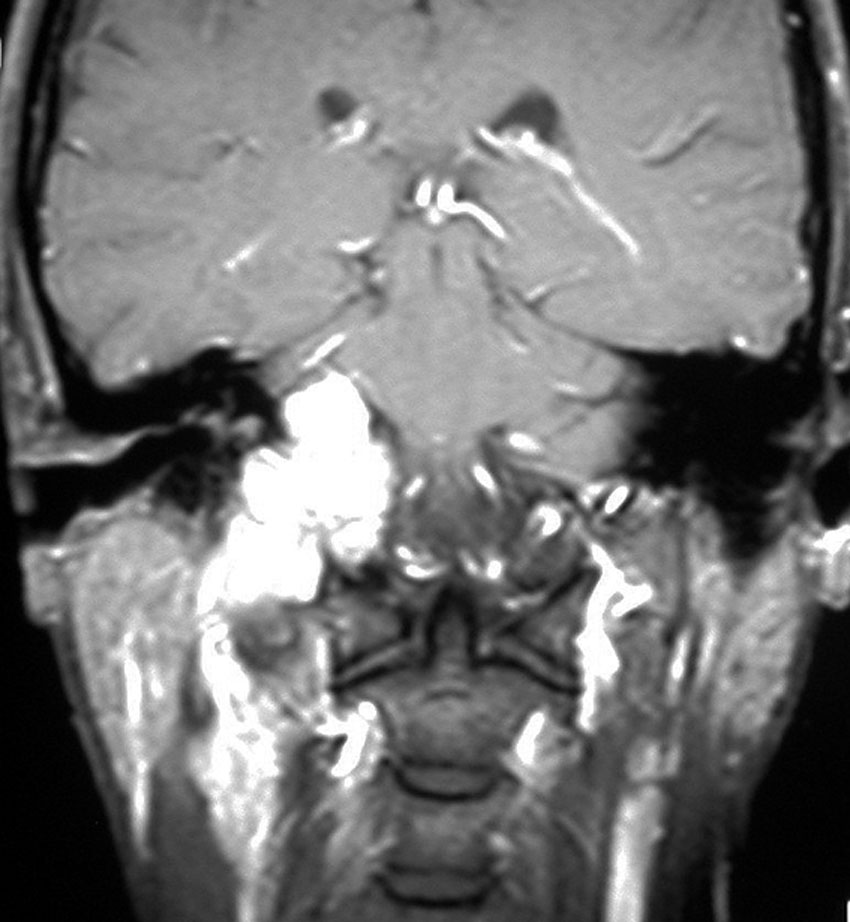

耳の聞こえと飲み込みが悪くなって発症(難聴と嚥下障害)した20代の患者さんのグロームス腫瘍 jugular paragangliomaです。左の頚動脈撮影 CAGでは,頸部の腫瘍におされて内頚動脈が前方に屈曲しています。外頚動脈から多くの血管が流入して血管腫のように濃い腫瘍陰影がみえます。右側の椎骨動脈撮影 VAGでは,頚静脈孔から頭蓋内の小脳延髄角部まで伸びた腫瘍が染まります。頭蓋内はPICAから頸静脈球と頸部には椎骨動脈の筋肉枝からの腫瘍血管がみられます。

頸部から頸静脈球を抜けてS上静脈洞内に入ります。これはクラスCかDか迷うところです。ちょっと難しい。またこのサイズでは,迷走神経と舌咽神経の機能を温存することができません。延髄方向へ伸展していますし年齢が若いので手術せざるを得ないものでした。

この腫瘍は放射線治療で制御できるものではないでしょう。手術で全摘出できて10年以上再発はありません。嚥下障害と強い嗄声が残りましたが,働いて社会生活はできています。